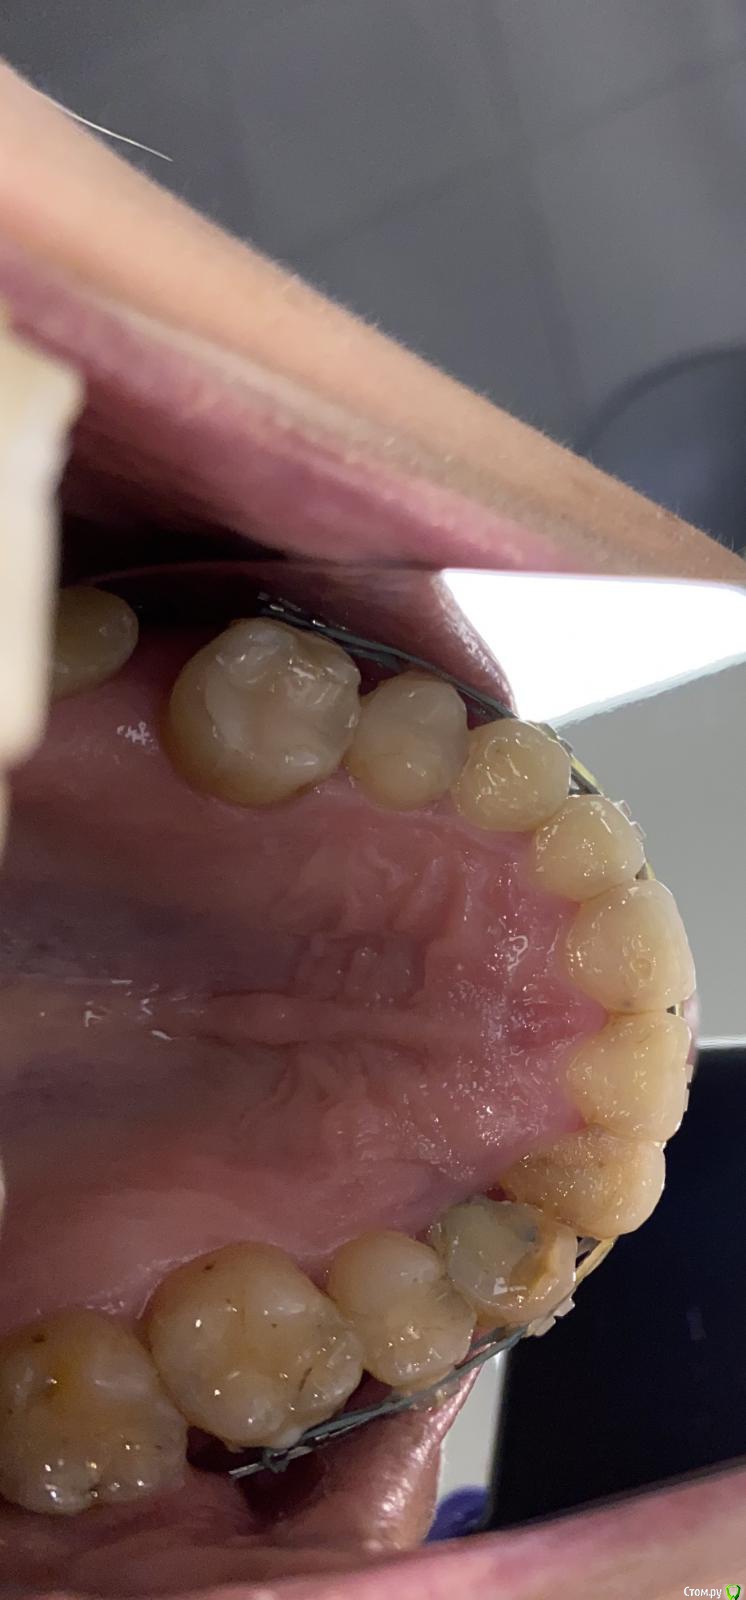

It'sGeorgy Опубликовано 4 июля, 2020 Поделиться Опубликовано 4 июля, 2020 Доброго времени суток!История такая: девушке (примерно 30-35 лет) в детстве был удален клык. После чего она перенесла 2 неудачных ортодонтии. Сейчас находится в процессе 3ьей попытки ортодонтического лечения. Пол года назад ситуация была такая: Сейчас такая: Котэ сделает в теч недели, прикреплю сюда же. Перкуссия 1.2 и 1.4 безболезненна. 1.4 без подвижности, 1.2 с I степенью подвижности. Само собой, как только снимут брекеты подвижность увеличится.Из личных мыслей: попробовать открыть, откюретажить корни, Эмдогейн, большой ССТ с бугра. Жду от этого небольшого прироста кости и "закрытия" кармана, чтобы внутрь перестала попадать пища.Всегда актуальный вариант: удаление обоих, мостовидная конструкция 1.1-1.5. Буду рад любым советам. Ссылка на комментарий

It'sGeorgy Опубликовано 4 июля, 2020 Автор Поделиться Опубликовано 4 июля, 2020 Проблема в плохих пломбах и гигиене. А также в ортодонтии пародонтита. Убирайте в топку брекеты и чистите зубки. ССТ закрывает рецессию, а не пародонтальный карман с анаэробами. Эмдогейн тоже сгниёт. Добейтесь ремиссии сначала. Ортодонту привет.Сразу уточню, что опыта ведения подобных пациентов у меня нет.Пол года назад, когда увидел пациентку впервые, именно ремиссии и попытался добиться. Сделали чистку, покюретажили. Сказали полоскать после приема пищи, купить ирригаторы. Оказалось бесполезно. Вчера пациентка сказала, что по ее мнению, не получается вычищать вот из-за этого участка. Возможно на фото не особо хорошо видно, но там огромное углубление:Собственно его я и хотел попробовать закрыть ССТ, отслоившись и подшив его небно. Спасибо за ваш совет. Будем начинать с чистки, снятия брекетов и замены реставраций. Если что-то интересное в итоге получится, скину результаты через пол года. Ссылка на комментарий